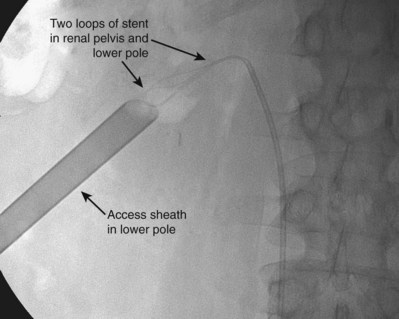

If ureteroscopic assistance is used, the first guidewire inserted into the kidney can be grasped with the ureteroscope and pulled down the ureter and out the external urethral meatus. With this through-and-through access, the guidewire cannot be lost. In all other situations, the goal for a therapeutic percutaneous procedure is to get two guidewires down the ureter into the bladder, generally a super-stiff (working) guidewire and a floppy tip or J-tipped PTFE-coated (safety) guidewire. One important exception is in cases in which a dependent lower pole has been accessed percutaneously. If there is extreme angulation to get from the lower pole calyx to the ureteropelvic junction and down the ureter, placing a super-stiff guidewire down the ureter may put undue force on the kidney and risk tearing parenchyma. In such cases, the flexible safety guidewire should still be directed down the ureter if possible, but the stiff working wire over which the dilation is performed can simply be directed toward the upper pole. Additionally, in some cases the pathology (e.g., calyceal obstruction, impacted ureteral stone, large staghorn stone) prevents the surgeon from getting a guidewire down the ureter or even into the remainder of the intrarenal collecting system. In such cases attempts should be made to get as much guidewire as possible into the upper urinary tract collecting system. A guidewire with a moveable core is useful in this setting because it can be coiled more tightly.

Once there is adequate wire access into the upper urinary tract collecting system, dilate the tract to allow insertion of working instruments. In most cases the goal of dilation for percutaneous renal surgery is to place a 30-Fr inner-diameter/34-Fr outer-diameter plastic access sheath. In some cases a smaller sheath, with an inner diameter measuring 12- to 24-Fr, is adequate. Renal access sheaths generally have a beveled tip, such that one side of the sheath extends farther than the other part. This bevel is used to maintain access into part of the collecting system on one side of the sheath while allowing extra mobility on the other side. Sheath repositioning is facilitated by the bevel. In cases of pathology at the edge of the collecting system, however, the bevel is a disadvantage because the entire tip of the sheath cannot be placed into the collecting system. Both opaque and clear sheaths are available; some prefer the clear sheaths because structures next to the sheath can be visualized.

Figure 47–27 Working sheath being passed over dilating balloon in lower pole access site. The working and safety guidewires are both going down the ureter.